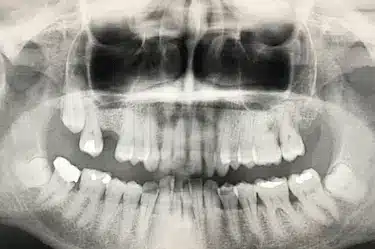

Paciente real del Dr. Ferrer que presenta la ausencia de una pieza dental.

Al no haber sustituido el diente perdido se ha producido una reabsorción ósea que ha provocado una disminución de la altura del hueso maxilar.

Antes del injerto de hueso dental solo había una altura de 5 mm para colocar el implante.

Para que el especialista pueda colocar un implante dental de forma estable y segura, es necesario una altura de hueso maxilar de al menos 8 – 10 mm.